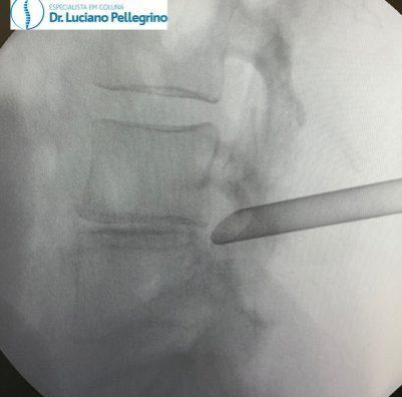

3. ENDOSCOPIA DA COLUNA PARA HÉRNIA DE DISCO

A endoscopia da coluna é uma das técnicas cirúrgicas mais modernas para tratar hérnias de disco.

Por se tratar de um procedimento rápido (costuma durar cerca de 1 hora) e minimamente invasivo, figura entre as alternativas preferidas quando sua indicação é possível.

Durante o procedimento, um pequeno tubo com uma câmera de alta resolução na ponta é inserido na pele do paciente por uma incisão mínima de 8 mm. Dessa forma, o cirurgião consegue visualizar as estruturas que compõem a coluna com clareza e manipulá-las com o auxílio de pinças e instrumentos especiais.

Assim como as microcirurgias, a endoscopia da coluna permite a retirada de fragmentos discais e ajuda a descomprimir nervos que podem estar causando dor.

Esse tipo de procedimento reduz as chances de lesões e complicações durante e após a cirurgia, já que a manipulação dos tecidos e estruturas da coluna é menor. Além disso, como a incisão necessária costuma medir menos de um centímetro, o tempo de recuperação é menor e na maioria dos casos o paciente recebe alta no mesmo dia. A anestesia pode ser geral ou apenas uma sedação, em casos selecionados.

cirurgia de hérnia de disco

Visualização da Cirurgia por Vídeo (endoscopia de coluna)

hérnia cirurgia

Endoscopia da coluna para hérnia de disco (visão do RX)